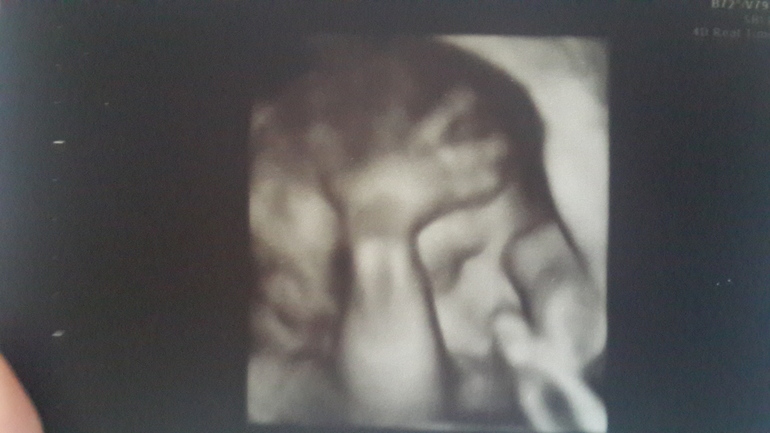

3D УЗИ 20.08.15

Море положительных эмоций и впечатлений! Сомнений нет,что сынуля!:) вес 1,2/1,3 кг, по месячным 27 нед и 2 дня , а по размерам на все 28! Спрогнозировали 4 кг! 0о_) делали в мед центре 1 доктор, отрадное, Северный бульвар 7б. Врач Сидорова Лилия - очень хорошее впечатление, все тщательно,внимательно,отлично просто. Цена 2600, диск и фото распечатали. Одно из фото